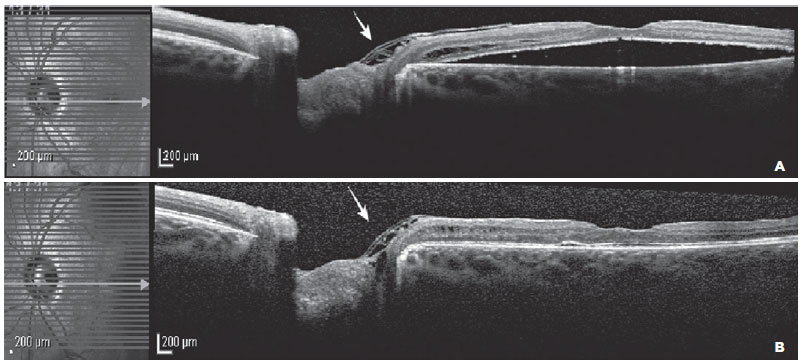

Gradual absorption of subretinal fluid was observed over 12 months of follow-up, and the BCVA improved to 20/30. The postoperative OCT examination confirmed the optic pit coverage by the inverted and folded ILM, as shown in figure 3.

11-fig03tb.jpg)